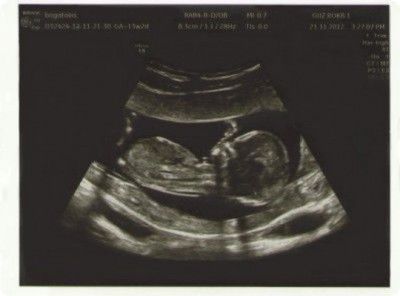

На 20 тижні вагітності чітко видно різницю між хлопчиком і дівчинкою в утробі матері. У міру зростання і розвитку малюка така різниця стає ще виразніше і на УЗД в 3 триместрі вагітності чітко видно: народитися син або дочка. Але за умови, що на момент ультразвукового дослідження навколо малюка буде потрібну кількість навколоплідних вод, що він не перехрестить свої ніжки. А таке трапляється досить часто!

Якщо говорити про результати УЗД на більш ранніх термінах виношування малюка, то визначення статі має свої особливості.

Медична статистика свідчить, що ймовірність помилки існує завжди. Дослідження точності визначення статі показали, що навіть при правильній позі дитини в момент УЗД досвідчені лікарі та сучасне обладнання визначають стать на терміні одинадцять тижнів з точністю до 70%. Коли ж термін зростає до дванадцяти тижнів, то точність становить дев'ять випадків з десяти.

Найостанніші дослідження говорять про те, що на терміні 12 тижнів точність діагностики статі по УЗД становить 46%, на терміні 13 тижнів - 80%.

Точно дізнатися стать майбутньої дитини на першому УЗД навряд чи вдасться. Сьогодні апарати ультразвукового дослідження не настільки високотехнологічні, щоб точно можна було розгледіти статеві ознаки плода. І до всього цього, лікар не буде чекати довго, поки малюку захочеться перевернутися і зайняти зручну для лікаря позу. До речі, на 13 тижні терміну дитина вже так крутиться в лоні майбутньої мами, що зловити потрібний доктору кут дуже складно.

Правильна візуалізація будь-якій частині плода залежить від багатьох факторів, таких як стан плода, кількість амніотичної рідини і товщина черевної стінки. Такі вдалі картинки як на фото зліва виходять украй рідко. У кого більше?